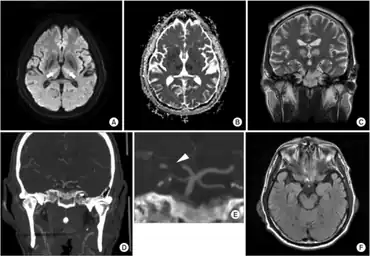

a) Axial diffusion-weighted imaging sequences b) diffusion coefficient image c)acute bilateral paramedian thalamic infarction d) CT angiography e)an unpaired thalamic perforating artery f) shows no midbrain lesion.

Diagnosis of pseudobulbar palsy is based on observation of the symptoms of the condition. Tests examining jaw jerk and gag reflex can also be performed. It has been suggested that the majority of patients with pathological laughter and crying have pseudobulbar palsy due to bilateral corticobulbar lesions and often a bipyrimidal involvement of arms and legs.[7] To further confirm the condition, MRI can be performed to define the areas of brain abnormality.